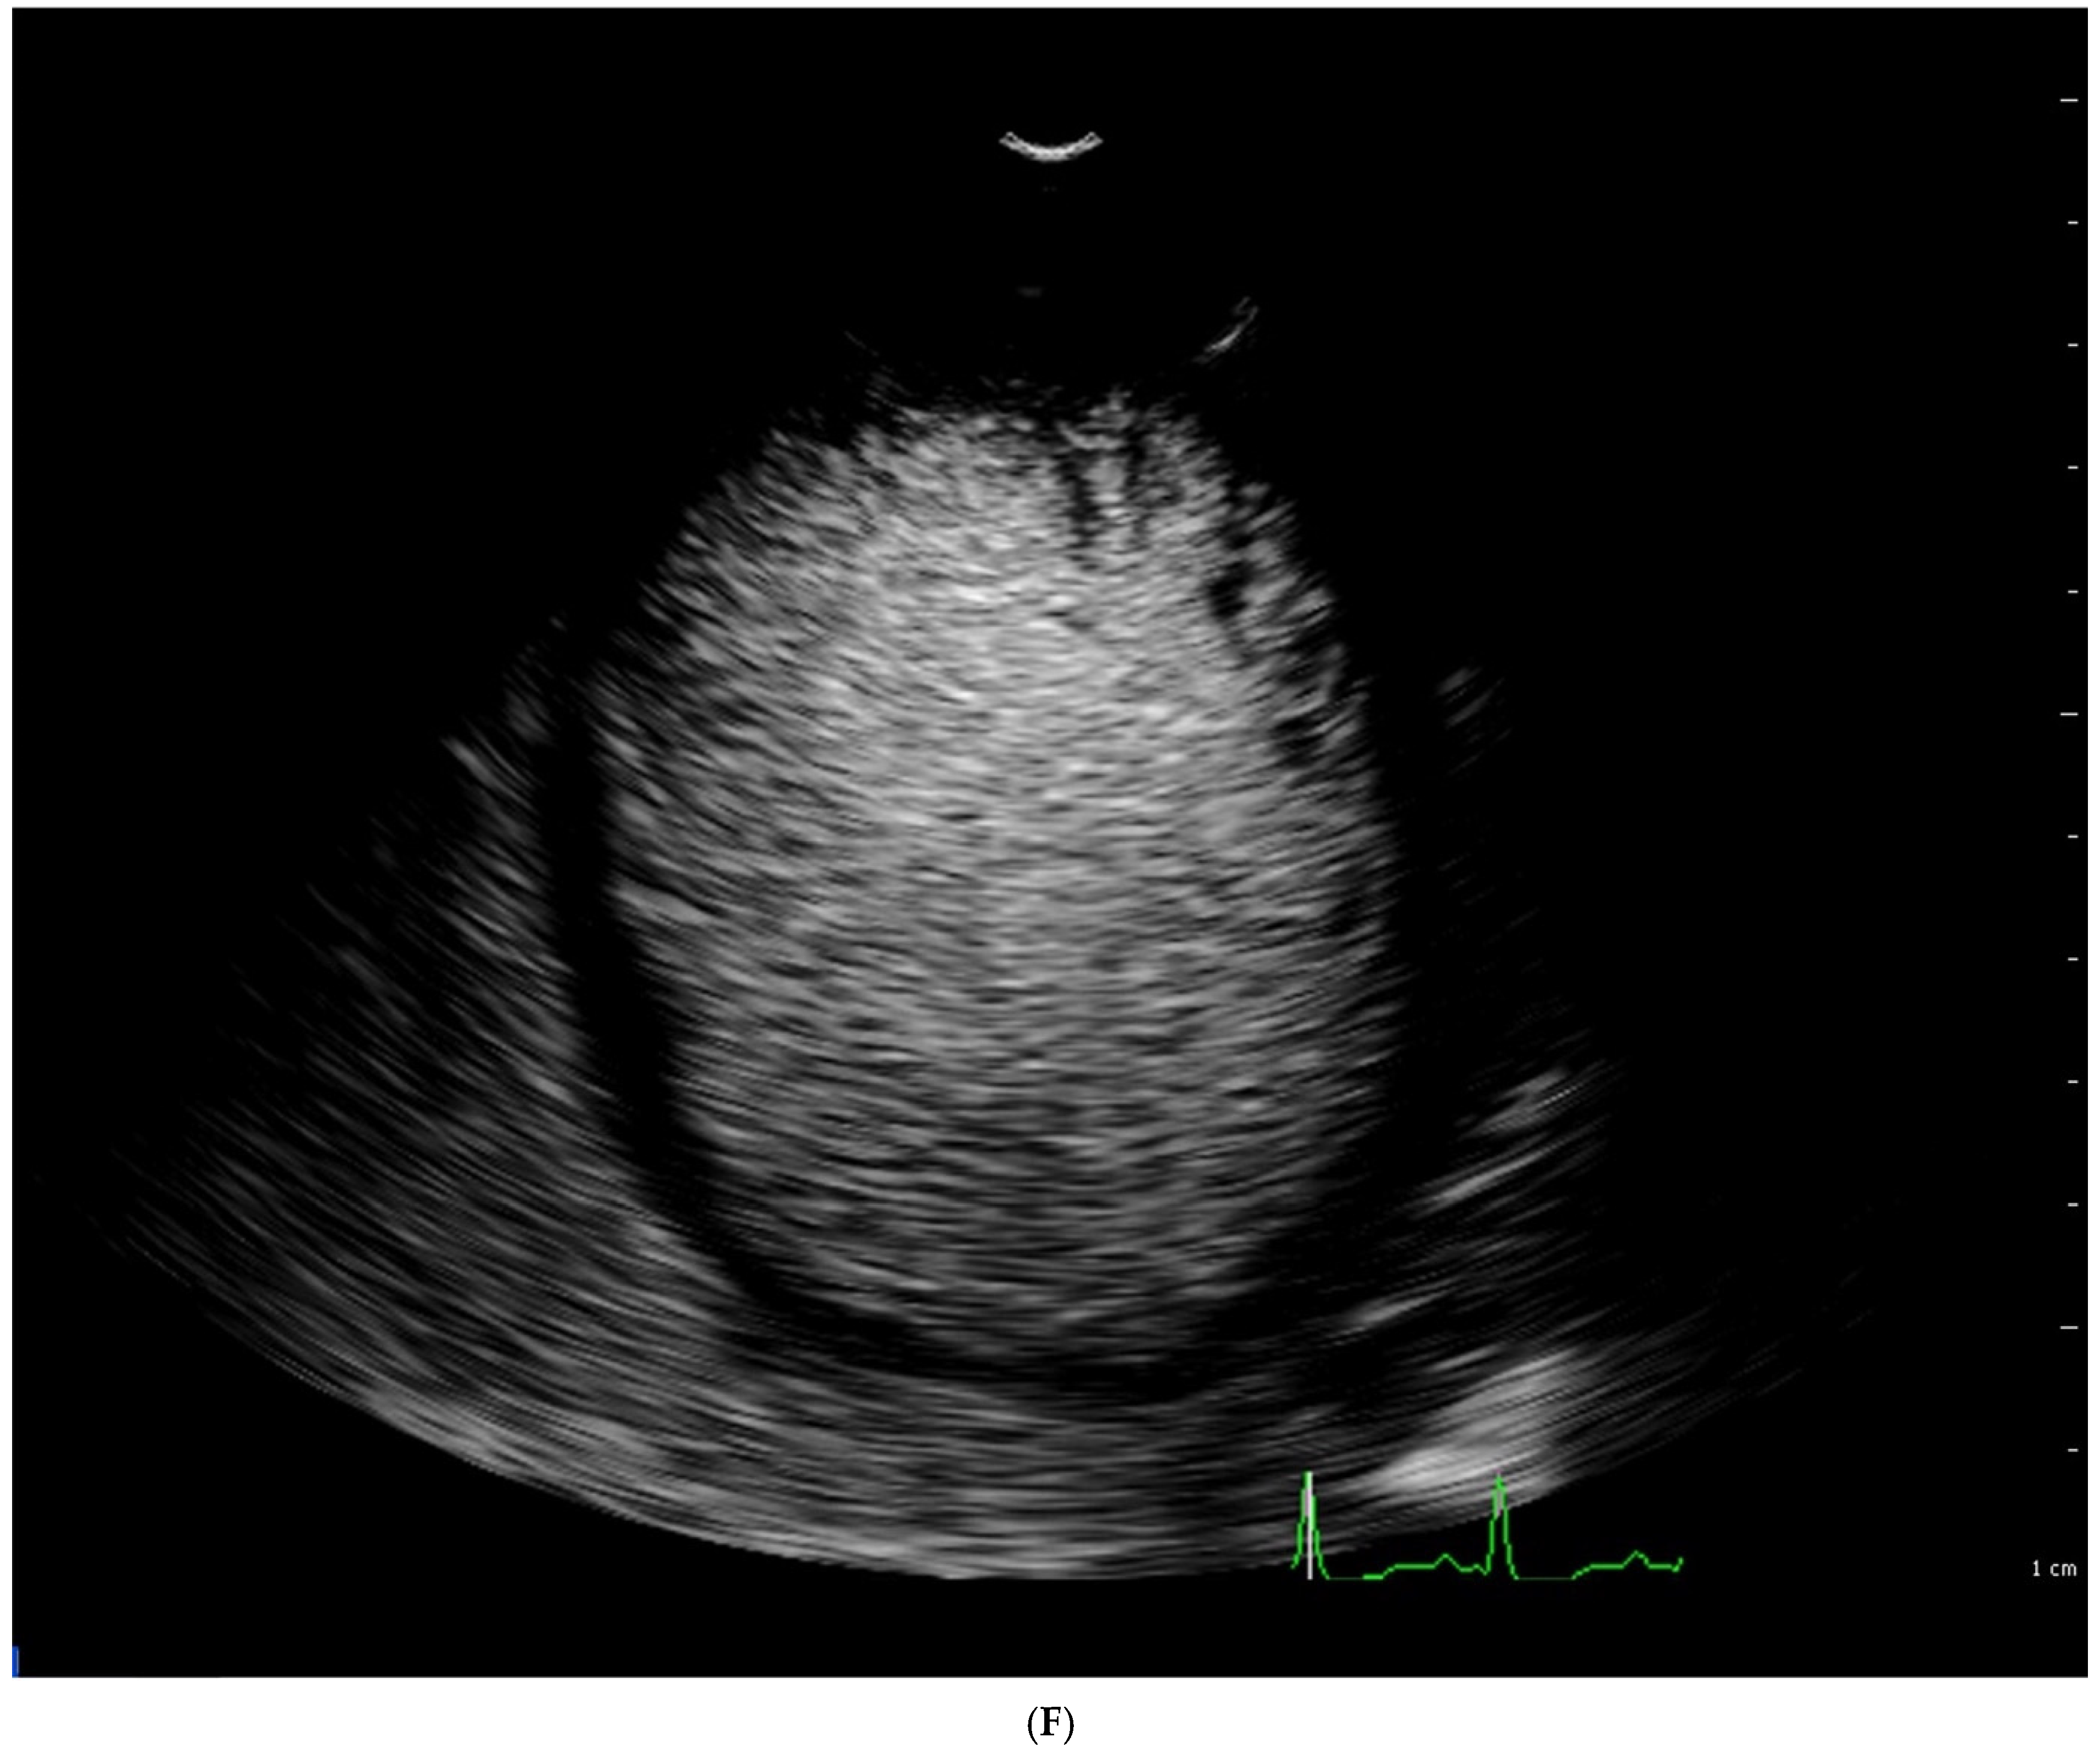

4.1. Echocardiography

| Stöllberger [47] | ECHO | Ratio of compacted and non-compacted endocardium. Presence of at least 3 trabeculations protruding in the left ventricle apically from papillary muscle, presence of the blood flow between trabeculations. | Four chamber, end diastole | NC/C > 2 |

| Jenni [33] | ECHO | Ratio of compacted and non-compacted endocardium. Absence of coexisting cardiac abnormalities, the presence of deep trabeculations, which are filled with blood | Short axis, end systole | NC/C ≥ 2 |